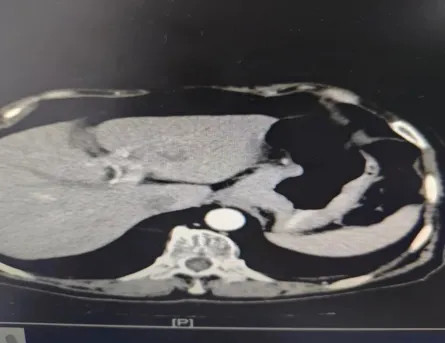

67歲吳依姆因患有尿毒癥,已經(jīng)持續(xù)血透4年了,近一個月以來逐漸進(jìn)食困難,身體每況愈下。經(jīng)過當(dāng)?shù)蒯t(yī)院胃鏡檢查,發(fā)現(xiàn)胃底賁門位有巨大潰瘍型腫物,病理結(jié)果證實為——“賁門下”神經(jīng)內(nèi)分泌癌(小細(xì)胞),且病情已發(fā)展到相當(dāng)嚴(yán)重的階段。術(shù)前CT影像顯示,腫瘤侵襲范圍廣泛,賁門至胃底部壁增厚,考慮MT并小彎側(cè)多發(fā)淋巴結(jié)腫大,腫瘤已阻塞了胃賁門(胃入口),這才使得吳依姆陷入無法正常進(jìn)食的狀況。

術(shù)前CT圖像